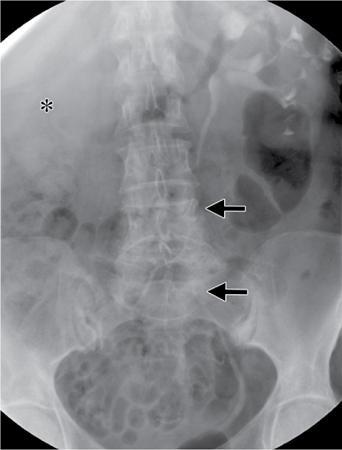

Image

Fig. 10.17.1.9 Contrast-enhanced axial (A, B) and sagittal CT (C) sections in a case of a perinephric haematoma (asterisks in A and B). It extends into the retromesenteric and retrorenal planes by means of bridging septae which traverse the perirenal space (blue arrow in A). Inferiorly, it extends along the combined interfascial plane into the pelvis (blue arrow in C).